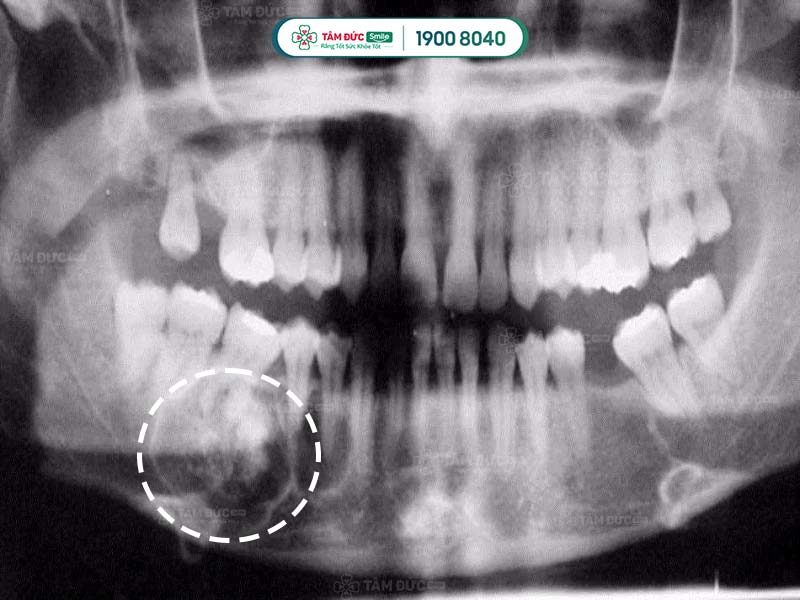

U răng qua phim chụp X-Quang

5.2. Chụp CT scan cho u răng

Sử dụng phương pháp chụp CT Scan để nhìn thấy rõ được cấu trúc bên trong khối u răng đó như thế nào.

Trong một số trường hợp cần thiết như u răng phức hợp phát triển vào khoang mũi. Cần thực hiện thêm 1 số xét nghiệm khác như chụp cộng hưởng từ MRI… Để có thể đưa ra được phương pháp điều trị phù hợp.